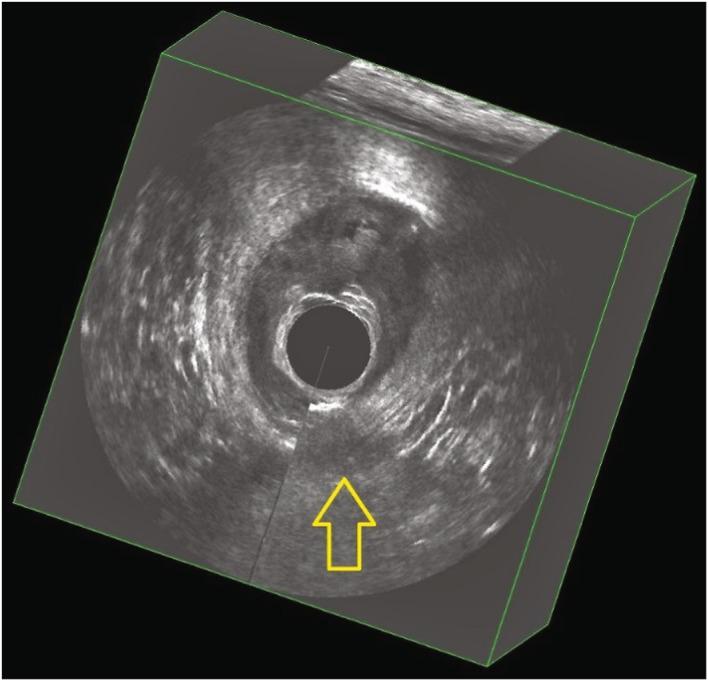

Obstetric anal sphincter injury (OASI) complicates around 5% of deliveries in primiparas. The study objective was to assess the utility of three-dimensional endoanal ultrasonography (3D-EAUS) in the diagnosis of OASI.

The present study was designed to mirror screening settings with an unselected cohort of nulliparous women. All enrolled patients underwent clinical examination of the perineum by the caregiver, and 3D-EAUS was conducted. Post-processing of ultrasonography volume data was performed by an experienced colorectal surgeon who was blinded to all other data. The sensitivity, specificity, negative predictive value, and positive predictive value of 3D-EAUS in the diagnosis of OASI was evaluated. The trial is registered at ISCRTN: 18006769.

A total of 680 scans were performed, of which 18.5% were judged as "non-assessable", resulting in 554 assessable recordings. Sphincter defects were observed in 12.8% of all assessable recordings on 3D-EAUS (n = 71). With clinical examination set as the reference standard, ultrasound sensitivity in the diagnosis of OASI was 30.4%, whereas its specificity was 87.9%. The negative predictive value was 96.7% and the positive predictive value was only 9.9%. Comments were left on 175 examinations, of which 74% referred to the management of the examination.

Using 3D-EAUS in a maternity ward is demanding because staff generally have little experience in endoanal ultrasound, which contributes to difficulties in obtaining good image quality. When 3D-EAUS is performed to mirror screening settings, it adds no convincing diagnostic power to clinical examination in the diagnosis of OASI.